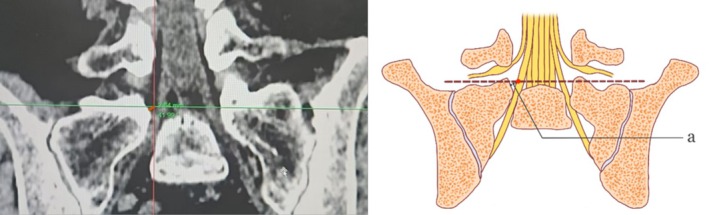

Objective: The first step of interlaminar endoscopic lumbar discectomy (IELD) is puncture localization, which lacks standardized protocols and requires a significant learning curve. To address this, we developed a modified corner approach targeting the junction of the S1 superior endplate and facet joint. This study aims to characterize the radiographic anatomy and assess the clinical utility of this modified approach.

Method: Computed tomography (CT) and magnetic resonance imaging (MRI) data from 100 patients were analyzed to measure distances between the target and adjacent structures (dura sac, pedicle, L5 nerve, and S1 nerve). The learning curve of interlaminar endoscopic lumbar discectomy (IELD) surgery based on the modified corner approach was determined by prospectively collecting data from 80 patients.

Results: The mean distance between the target and the dura sac was 4.59 ± 1.74 mm. The mean distance between the target and the inferior border of the L5 nerve was 10.14 ± 1.72 mm, rang from 7.52 to 13.54 mm. The mean distance between the target and the outer edge of the S1 nerve was 0.51 ± 0.91 mm, rang from -0.12 to 2 mm. The mean distance between the target and the inner edge of the S1 pedicle was 3.77 ± 1.04 mm. The distance between the target and the dura sac and the inner edge of the pedicle is mainly affected by the patient's age.

Conclusion: The modified corner approach is a simple, safe, and repeatable surgical approach with the intersection of the superior endplate and facet joint as the puncture target. For patients without or with mild facet joint degeneration, the puncture target can be appropriately moved inward by 2 mm.